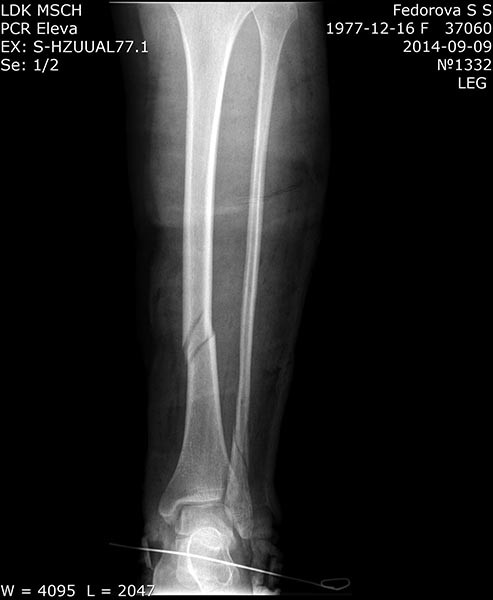

Есть ли альтернатива БИОС в данной ситуации?Добрвый день. Пациентка 37 лет, соматически здорова.04.09.14г. Подвернула левую ногу, получила винтообразный перелом обеих костей н/з левой голени со смещением отломков.

В ЦРБ наложено скелетное вытяжение за пяточную кость. При рентгенографии на вытяжении смещение отломков большеберцовой кости устранено. Доставлена к нам на 4-е сутки в задней гипсовой лонгете. Вот снимки при поступленни к нам в гипсе. Ваши предложения по тактике лечения данного перелома?